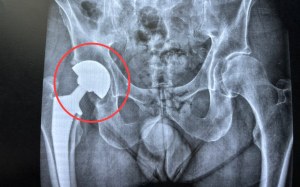

Depuis quelques semaines, ma hanche ne me fait plus mal quand je marche, et par conséquent, mon genou non plus. Fin mars, je suis allé à l’hôpital pour recevoir une prothèse. L’après-midi suivant l’opération, j’ai déjà fait mes premiers pas. Avant d’y aller, j’étais conscient que la prothèse était un cadeau de la vie bien mérité, car j’avais compris, intégré ou modifié ce qui était nécessaire. Je savais aussi que si quelque chose restait incompris, je le saurais grâce à un problème qui apparaîtrait ou une douleur qui persisterait. Et ça n’a pas loupé. En marchant, j’ai remarqué qu’il y avait du jeu dans l’articulation. La rotule sortait partiellement de son alvéole et le claquement interne que ça produisait résonnait jusque dans ma tête. C’était très inconfortable et lorsque j’essayais de me faire entendre, les mots que j’entendais systématiquement étaient « c’est normal ». Pourtant, le chirurgien n’avait jamais vu ça…🩼

Si vous comparez les deux cercles rouges, vous voyez qu’à gauche,

quand je détends ma jambe, la rotule sort de l’alvéole…